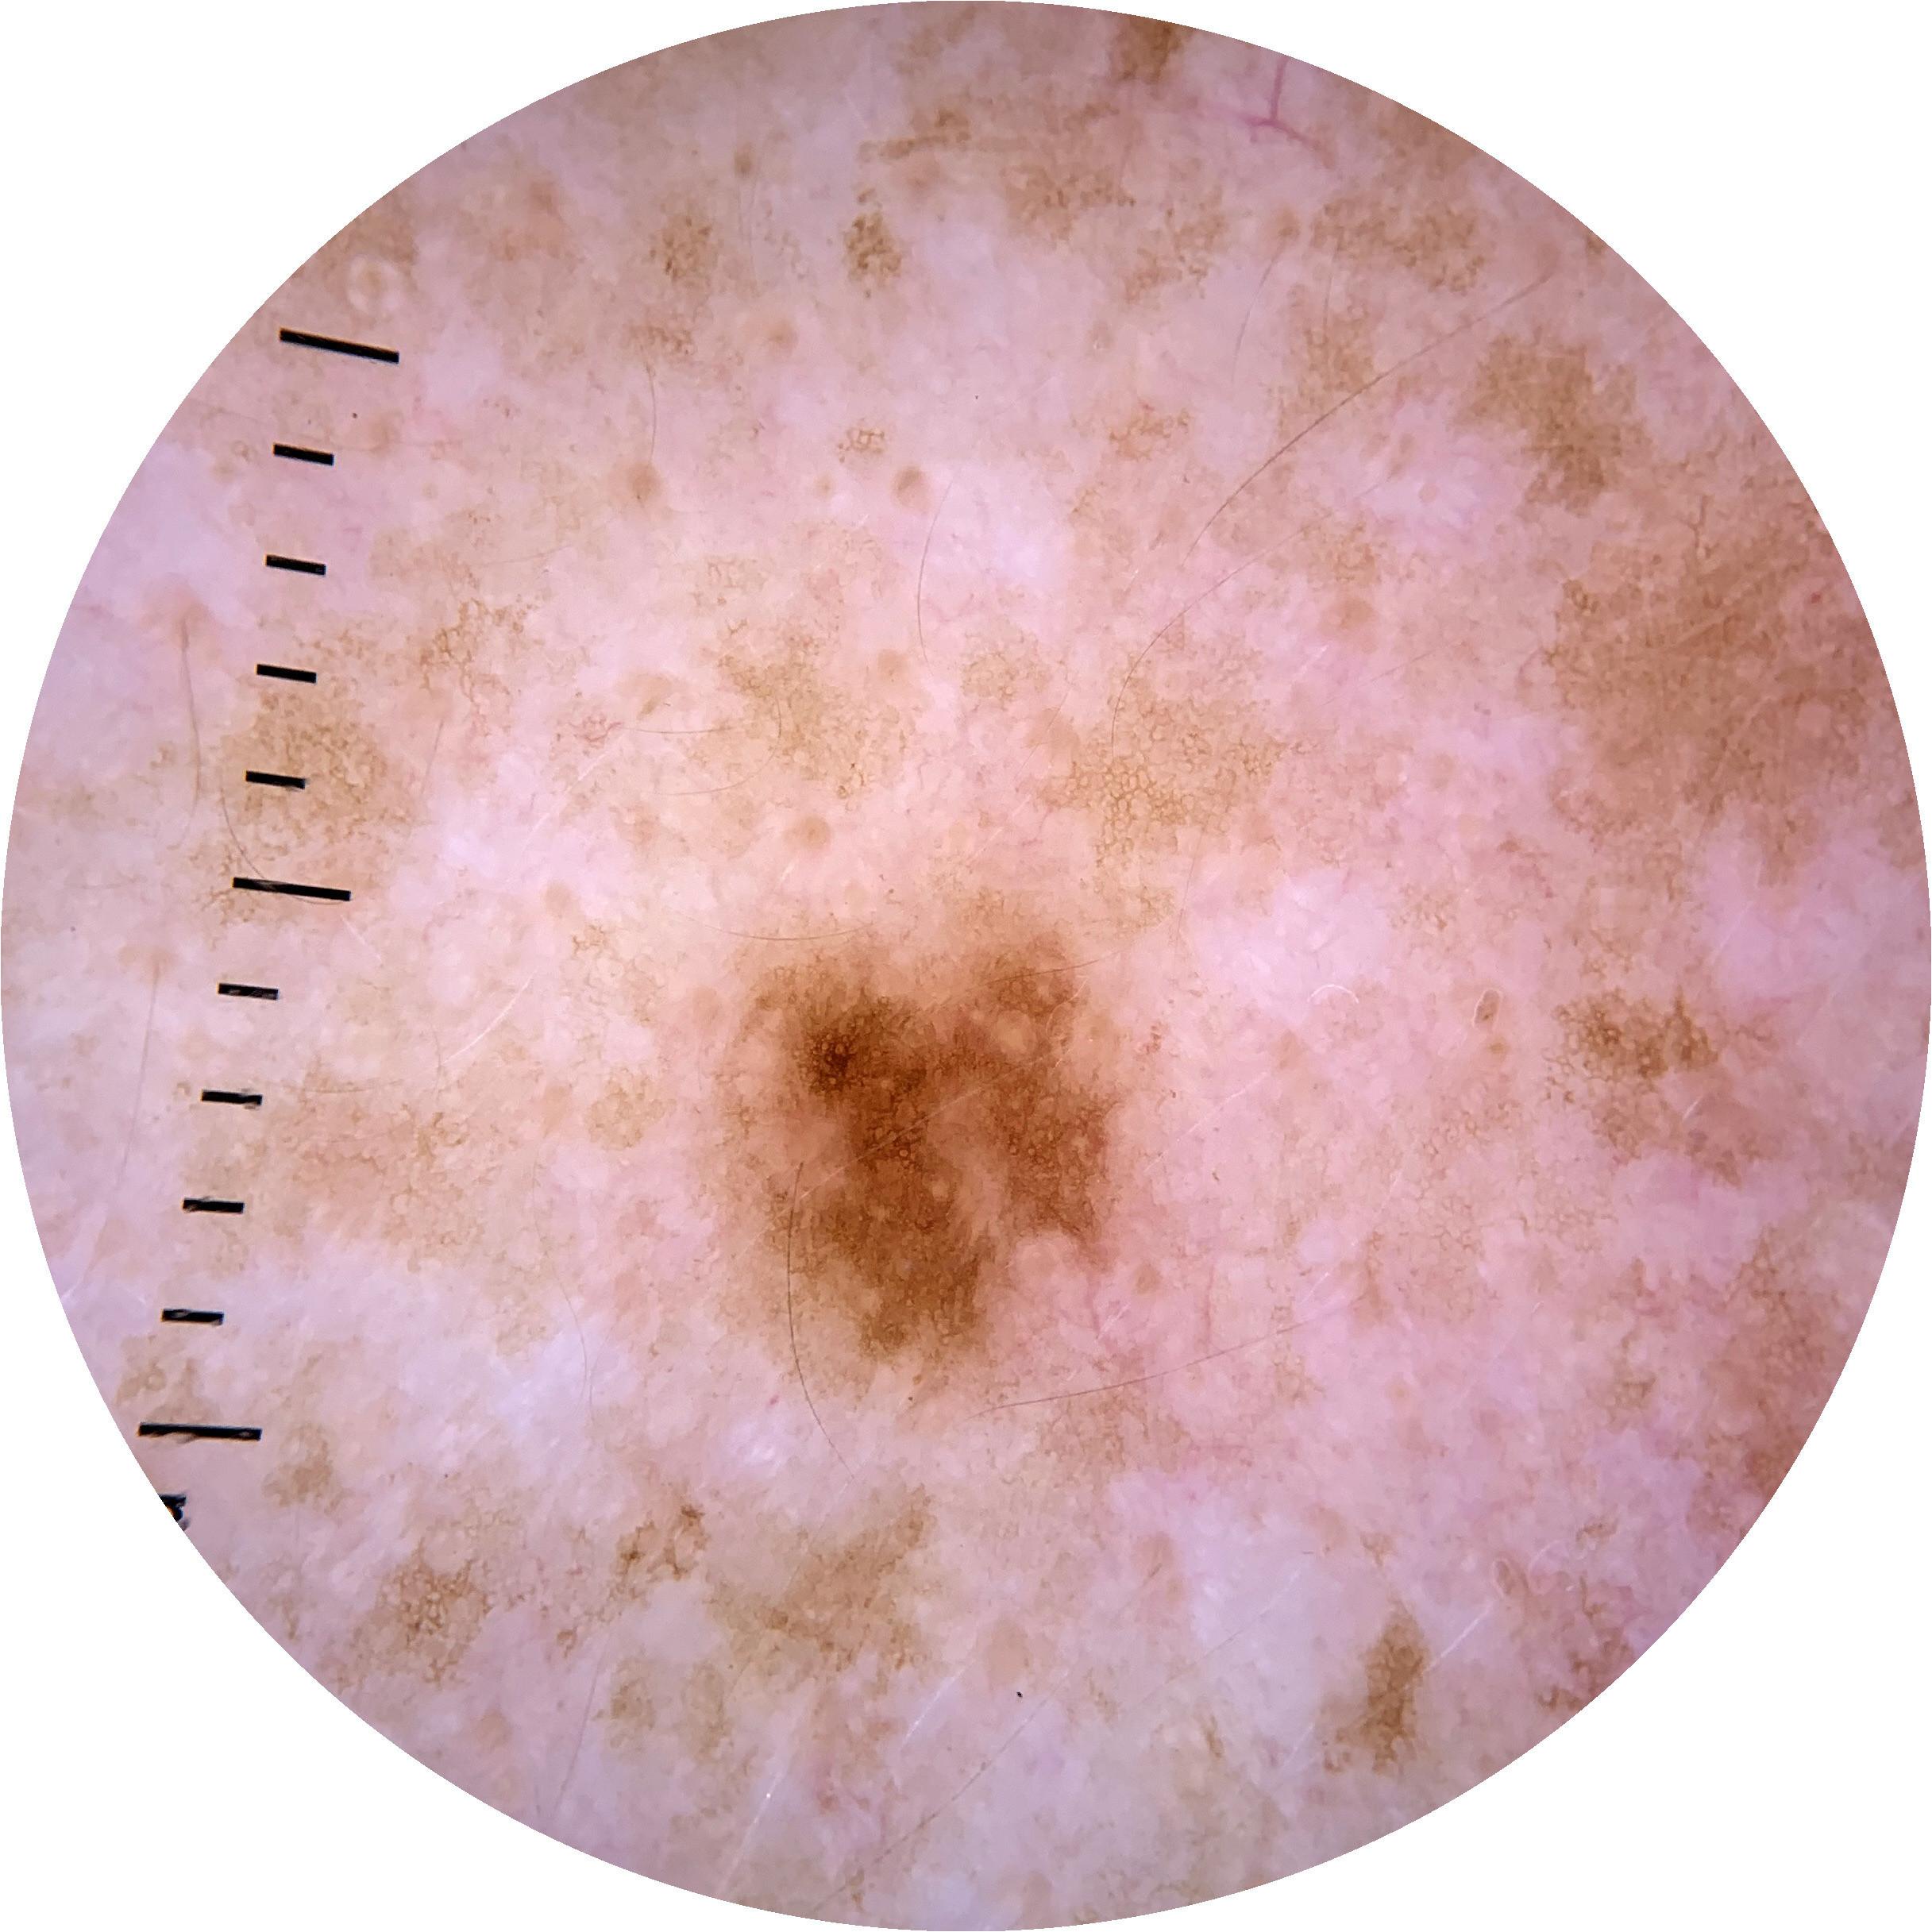

ISIC_4923598

1979 x 1979

Clinical

Field Value

acquisition_day 242

age_approx 45

anatom_site_1 Trunk

anatom_site_2 Posterior trunk

anatom_site_general posterior torso

diagnosis_1 Benign

diagnosis_confirm_type single image expert consensus

image_type dermoscopic